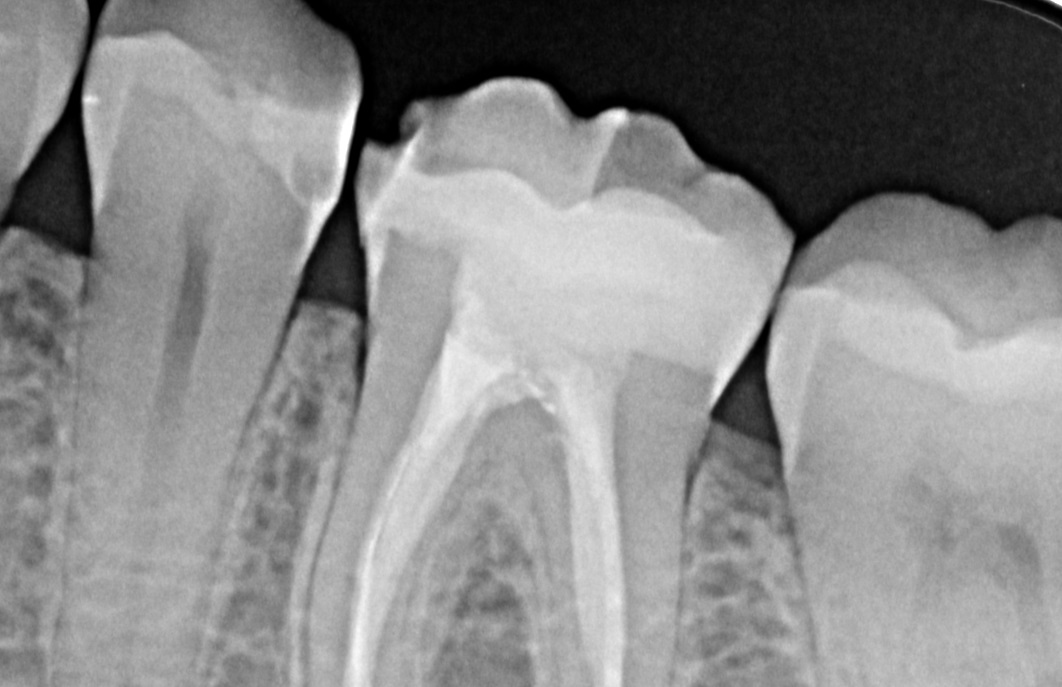

PROFUNDA Caries Dental ocurre como un proceso dinámico y complejo en el que interactúan el biofilm bacteriano y la superficie del diente (Kidd 04) Diente con caries profunda Diente asintomático ,sin historia de dolor o con diagnóstico de pulpitis reversible RADIOGRÁFICOS Radiografía. Esta técnica se aplica cuando los dientes están fracturados, con caries profundas o lesionadas en su tejido pulpar (tejido conectivo laxo) en las que se da una sintomatología característica pulpitis La endodoncia rotatoria es una técnica innovadora para la extirpación del nervio dañado y mantener la pieza dental. Normalmente una caries profunda de da sintomatología de dolor en el 90% de las ocasiones se ve claramente Ver respuesta Hola, se puede hacer una endodoncia en el mismo diente donde te han hecho un empaste.

Cómo identificar un absceso dental Un absceso dental es una infección bacteriana dolorosa que hace que se forme y se acumule pus en la raíz del diente o entre el diente y la encía Los abscesos suelen aparecer como consecuencia de una. Dolor adolorido cuando la comida entra a la cavidad cariosa;. PROFUNDA Caries Dental ocurre como un proceso dinámico y complejo en el que interactúan el biofilm bacteriano y la superficie del diente (Kidd 04) Diente con caries profunda Diente asintomático ,sin historia de dolor o con diagnóstico de pulpitis reversible RADIOGRÁFICOS Radiografía.